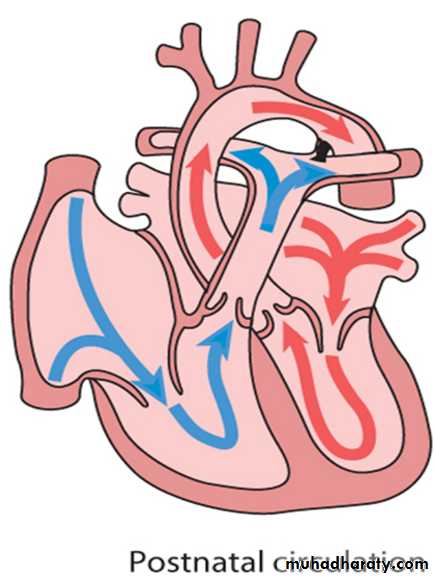

Circulatory changes at birth

In the fetus, the left atrial pressure is low, as relatively little blood returns from the lungs.

The pressure in the right atrium is higher than in the left, as it receives all the systemic venous return including blood from the placenta.

The ductus arteriosus shifts the blood from the pulmonary artery to the aorta.

Congenital heart disease

The flap valve of the foramen ovale is held open, blood flows across the atrial septum into the left atrium and then into the left ventricle, which in turn pumps it to the upper body.

With the first breaths, resistance to pulmonary blood flow falls and the volume of blood flowing through the lungs increases sixfold. This results in a rise in the left atrial pressure. Meanwhile, the volume of blood returning to the right atrium falls as the placenta is excluded from the circulation. The change in the pressure difference causes the flap valve of the foramen ovale to be closed. The ductus arteriosus will normally close within the first few hours or days.